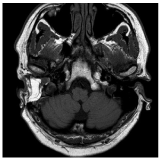

At the age of 37 the Patient (Pt) presented a sudden headache and then a stiffness of the nuchal region after a trivial neglected right otitis media. A post-traumatic pathological pathway between middle ear and the posterior cranial fossa was evidenced with a urgent CT (Figure 1). The new otogenic meningitis was confirmed with a MRI (Figure 2), wich showed an abscess of the brainstem. This infection has regressed thanks to medical therapy alone.

Figure 2. Pre-surgery MRI: right otitis media associated with an abscess involving the brainstem and the right cerebellar peduncle (the fistular connection between the middle ear and the ponto-cerebellar angle is clearly evident)